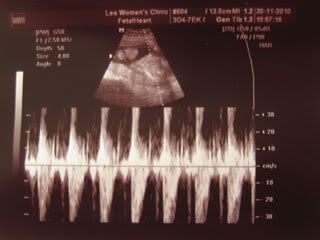

Her heartbeat.